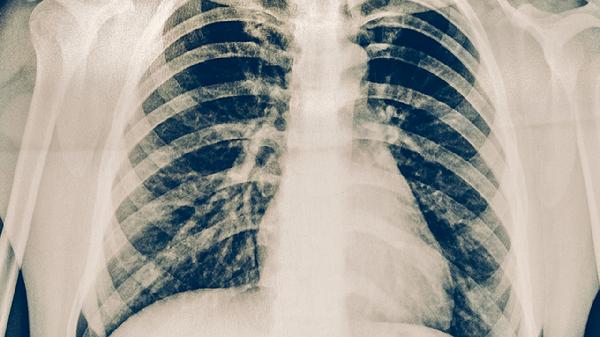

胸部X線或CT檢查可發(fā)現(xiàn)肺結(jié)核的典型表現(xiàn),如上肺野浸潤(rùn)影、空洞形成或纖維鈣化灶。影像學(xué)特征有助于判斷病變范圍和性質(zhì),但需與肺炎、肺癌等疾病鑒別。活動(dòng)性肺結(jié)核常表現(xiàn)為斑片狀陰影伴空洞,陳舊性結(jié)核則以纖維條索影為主。